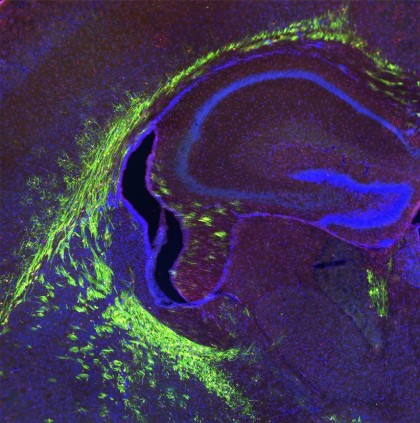

foto: Creierul modelului preclinic în curs de dezvoltare cu axoni mielinizați (prezentați în culoarea verde) // Credit: Vetrivel Sengottuvel

În studiul actual, echipa de cercetători a arătat în modelele preclinice că eliminarea Mfsd2a din celulele precursoare care se maturizează în celule producătoare de mielină din creier a dus la mielinizare deficitară după naștere. Investigațiile ulterioare au demonstrat că absența Mfsd2a a determinat reducerea grupului de molecule de acizi grași în celulele precursoare, împiedicând aceste celule să se maturizeze în oligodendrocite, care produc mielină.